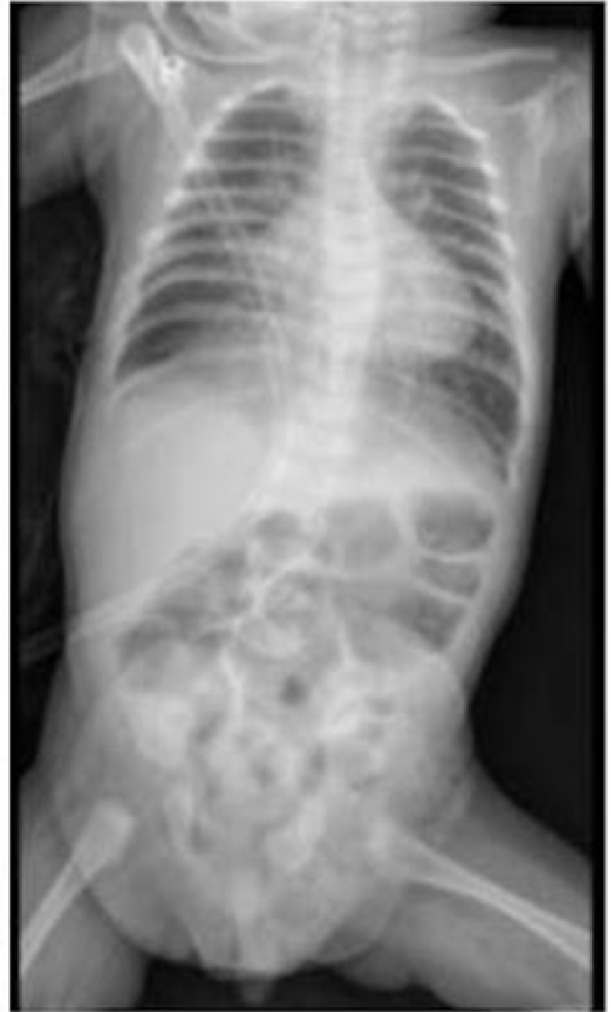

Se presenta un caso clínico de un lactante de 38 semanas de edad, procedente de la ciudad de Chiclayo en Perú, quien fue ingresado a la sala de emergencias del Hospital Regional Lambayeque por un cuadro febril y dificultad respiratoria, seis horas después de su ingreso, se acentuó el distrés respiratorio, lo que llevó a la intubación y conexión a ventilación mecánica invasiva. Tras la evaluación de los resultados de Radiografía (Figura 1) se inició el tratamiento antimicrobiano con Ceftriaxona y Azitromicina, junto con sedoanalgesia a base de Midazolam y Fentanilo.